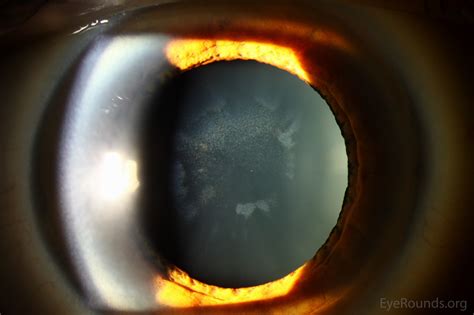

The most famous and recognizable symptom associated with Wilson Eye Disease is the Kayser-Fleischer (KF) ring. These rings are caused by the deposition of copper granules in a specific layer of the cornea called Descemet's membrane. Think of them as tiny, shimmering copper dust that settles right at the edge of your iris.

What do KF rings actually look like? They appear as yellowish-brown, reddish-brown, or sometimes greenish rings that encircle the edge of the cornea. They typically start at the top of the eye and spread to completely surround the iris.

It's important to note that you often won't notice these rings yourself, especially in their early stages. A doctor needs a special tool called a slit lamp to see them clearly. In nearly all patients who have neurological symptoms of Wilson Disease, KF rings are present; however, they may be absent in those who only present with liver symptoms.